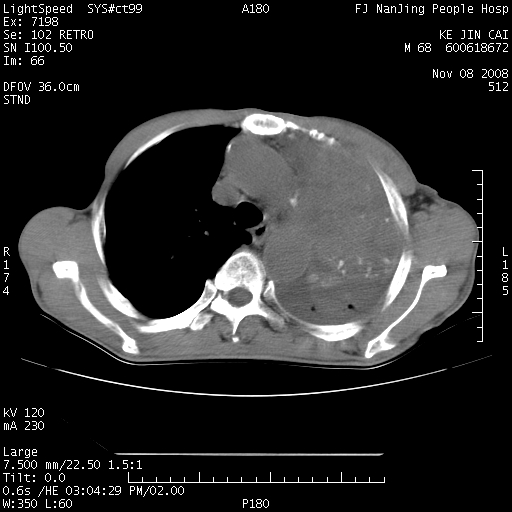

是个很有看头的病例,咋人气那么不旺?没多少人兴趣呢?这个病例几大怪:1   恶性肿瘤侵犯心肌左房怪,心肌一般不会被恶性肿瘤侵犯吧?2   左下肺均匀实变怪,内无含气,有别一般不张实变,含气肺泡完全为液体取代,而非一般不张实变的肺萎陷,冷不丁还以为是肿大的脾脏3   肿瘤本身怪,像tb肺不张4   这么有看头的病例没人气怪。呵呵。

左肺恶性肿瘤侵犯肺动脉,左心房内瘤栓,胸膜转移。